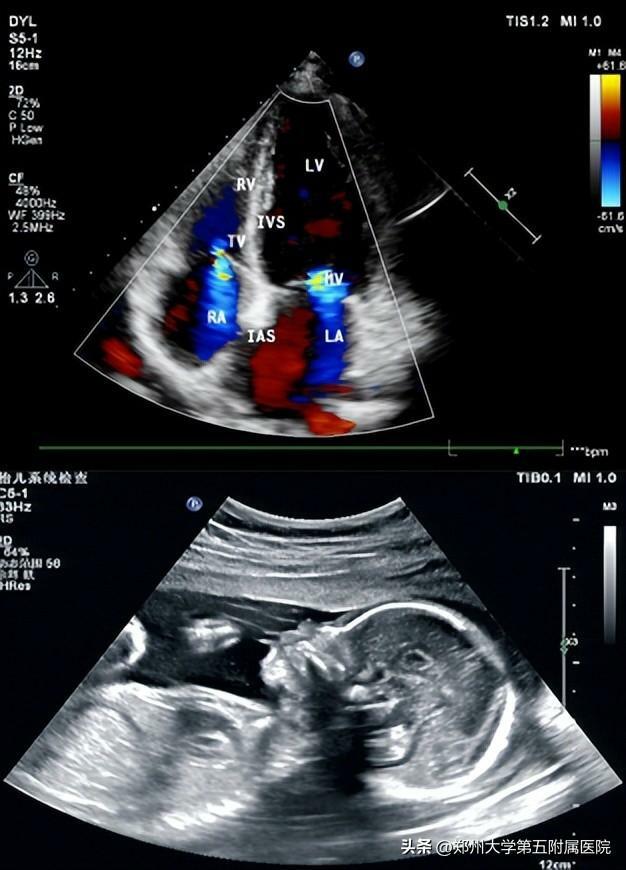

04超聲

超聲波(指頻率20000赫茲以上的聲音,人耳已無法聽到)和普通的聲音一樣,能向一定方向傳播,而且可以穿透物體,如果碰到障礙,就會產生回聲,不相同的障礙物就會產生不相同的回聲,人們通過儀器將這種回聲收集並顯示在屏幕上,可以用來了解物體的內部結構,利用這種原理人們將超聲波用於診斷和治療人體疾病。超聲檢查沒有輻射!